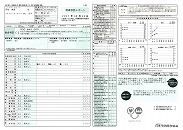

092 病院定期検査

2024-0210西原クリニック検査結果

090 脳ドック

2024.18.14 荒尾市民病院 2023.08.10 荒尾市民病院

2024 PDF 2023 PDF

22.9.16 荒尾市民病院

2014(H26)7.29 岡山淳風会